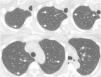

We present a case of a 48-year-old female, with previous history of seizures and TSC diagnosed 18 years earlier, based on the presence of skin lesions (facial angiofibromas) and cortical tubers on brain MR. Investigation of her family revealed that 6 relatives have the same condition. She is a non-smoker and has had no relevant occupational exposure. The patient presented asymptomatic, namely without respiratory complaints. The pulmonary function tests were normal: FEV1 2.91L (104% of predicted); FVC 3.6L (110% of predicted); DLCO 81%. Abdominal CT were performed to assess renal angiomyolipomas; the lower parts of the lungs showed pulmonary nodules that were followed up with a chest CT. The chest CT revealed multiple ground-glass nodules scattered through both lungs, the largest one was 8mm (Fig. 1). There were no cystic lesions suggestive of LAM. After 2 years of follow-up the nodules remained stable in size and number, compatible with a MMPH diagnosis.

MMPH, despite being considered rare, is the second most common cause of lung involvement by TSC. This disorder consists of multicentric, well-demarcated nodular proliferation of type II pneumocytes along alveolar septa, and has been reported in men and women with TSC (with or without LAM manifestation) and in women with sporadic LAM, with only 3 cases described without this association.3 Clinically, MMPH might be associated with cough, dyspnea and moderate or asymptomatic hypoxemia.2 Unlike LAM, treatment is generally not needed in MMPH, because it seems to be indolent and not progressive, moreover it has not been proven to have malignant potential.4 On HRCT MMPH is characterized by multiple solid or ground-glass nodules, ranging from 2 to 10mm, scattered through the lungs in a random distribution. The main radiological differential diagnosis includes atypical adenomatous hyperplasia, early Langerhans histiocytosis, hematogenous metastases and miliary tuberculosis. The differentiation between MMPH and these entities may be very difficult, however the history of TSC, the multiplicity and random distribution of the nodules, as well the stability of number and size of these lesions in the follow-up examinations, helps to provide the diagnosis MMPH.